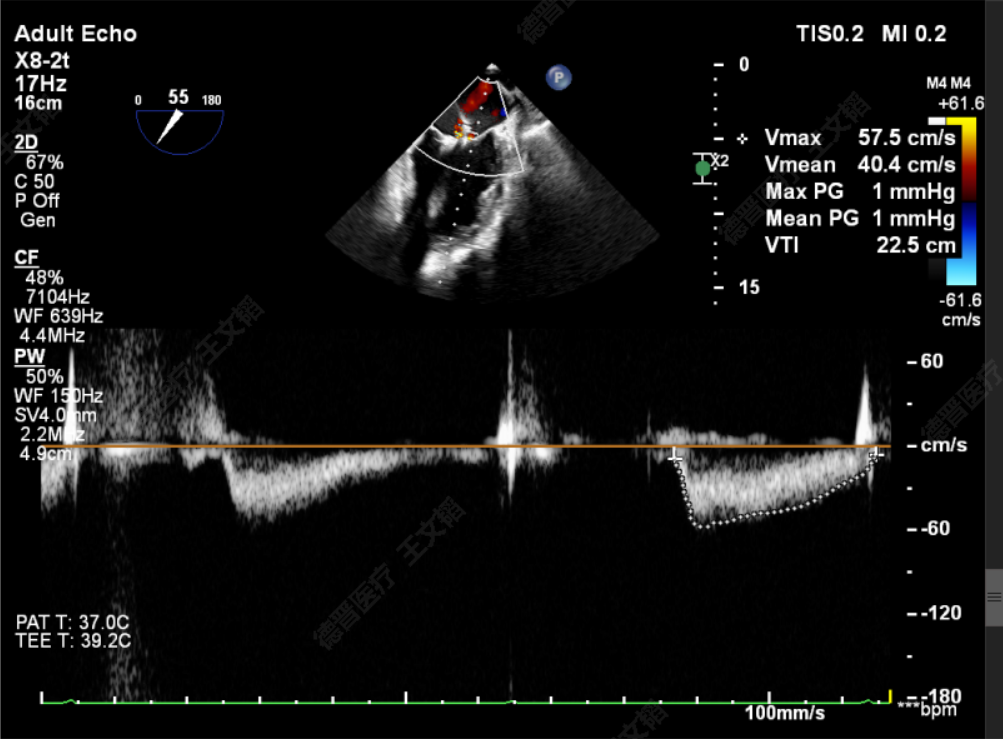

术中鄢华院长团队宋丹主任、郭卉主任与超声科余正春教授经充分沟通及分析,决定术中采用拉链式策略,先在2区偏3区植入1枚短宽二尖瓣夹,术中房间隔穿刺高度:4.2cm,于2区偏3区置入一枚短宽瓣膜降低瓣叶张力、减少撕裂风险,夹闭后瓣叶张力可、夹子L侧仍残余反流2-3+。于是再于2偏1区置入第二枚短宽瓣膜夹,夹闭后反流降至轻度,跨瓣压差1mmHg,肺静脉逆流消失。

TMPG:1mmHg

肺静脉逆流消失